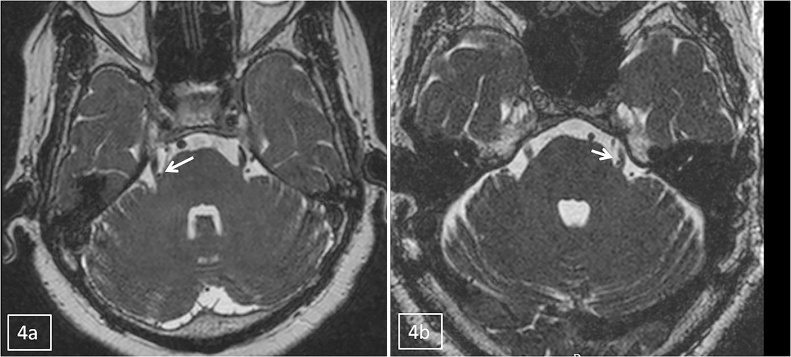

The neurovascular contact between trigeminal nerve and vessel was seen in 41 (80.4%) cases (Fig. 2) though this is significant (p < 0.001) but NVC was also seen in 17 (28.3%) controls (Table 2). To say with conviction that there exists a conflict between the offending vessel and nerve, merely a lone criterion of presence of NVC is not sufficient. Other criteria studied in this study were the anatomical changes in the nerve which are more frequently seen in the REZ were thinning in caliber of nerve, arterial imprint/grooving on the nerve or distortion of the course of nerve. The thinning in caliber of trigeminal nerve (Fig. 3) was seen in 52.9% cases, arterial imprint/grooving on the trigeminal nerve (Fig. 4a and b) was seen in 50.9% cases and distortion of the course of trigeminal nerve (Fig. 5) was seen in 23.5% cases, these findings were significant with p < 0.001. Also the post hoc power for NVC, thinning of caliber and arterial imprint was 100% and for distortion of course of nerve was 94.52%. All these anatomical changes in the nerve result in the focal demyelination or stretching of nerve which is the basis of symptoms in these patients as discussed above therefore these findings are highly significant as they point toward a potential conflict between the nerve and the vessel. Sherif et al. in their study reviewed MRI of 782 cases of neurovascular compression to analyze the imaging criteria and found that distortion of course of nerve and reduction in caliber of nerve were significant findings, however they did not consider arterial imprint/grooving on the nerve in their study and the findings were not compared to control group which was done in this study.6

Fig. 4.

(a and b) Axial images of two different patients showing vascular loops at root entry zone with arterial imprint/grooving on the trigeminal nerves (arrow).